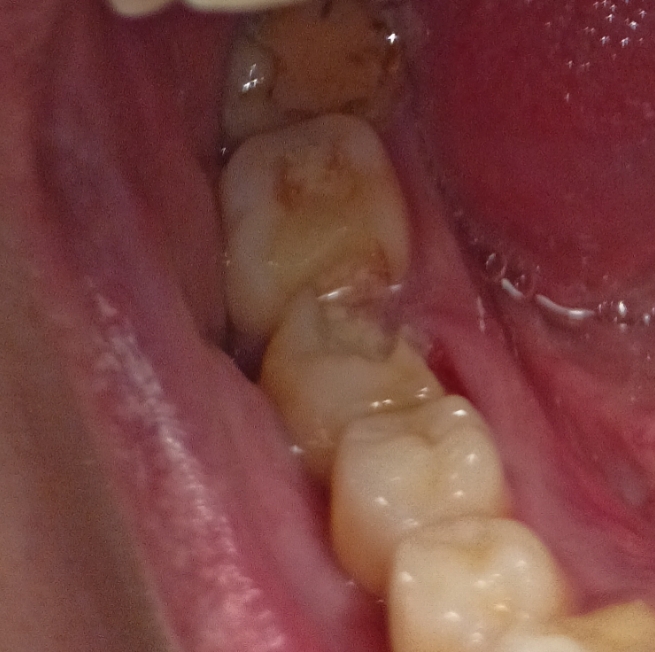

3968x2976

Че будет завтра со мной?

Аноним 11/08/25 Пнд 16:43:32 1635630 37